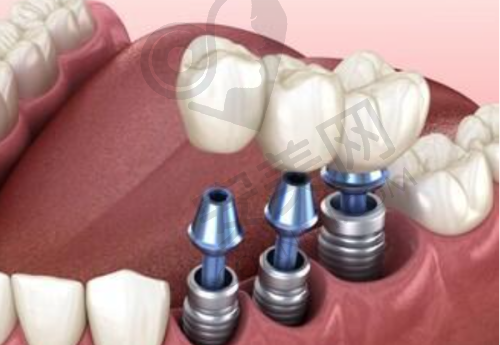

技术是种植牙的核心。沈阳国民口腔在这方面表现突出。在设备上,配备了德国卡瓦CBCT体层摄影系统、光纤定位种植机等精良设备,这些设备可有效评估骨量、规划种植路径,从而降低手术风险。

在技术方案上,提供微创种植、多颗联合种植、半口/全口即刻负重等方案。其中,即刻负重技术可实现“当天种牙当天用”,大幅缩短了治疗周期。对于骨量不足的患者,采用骨增量技术,避免了传统植骨的高昂费用和漫长等待时间。例如,2025年6月3日,一位牙槽骨吸收的患者,通过骨劈开术 + 种植,节省了1.2万元植骨成本。

同时,该医院的种植修复专科还开展了小创口即刻种植、ALL - ON - 4全口种植修复等特色项目。传统种植牙手术创口大、修复时间长,而小创口即刻种植能在拔牙后马上种牙,创口小,大大缩短了治疗周期,减轻了患者痛苦。